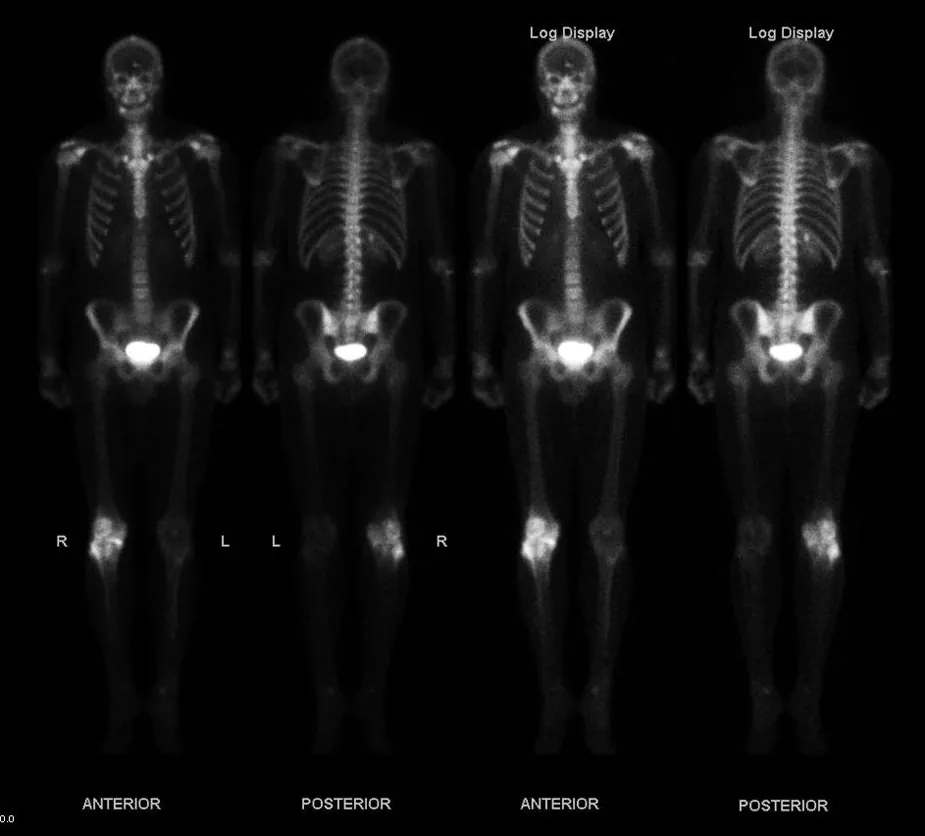

This figure shows four images of a skeleton of a human. Different parts of the body show bright spots wherever the bone cells are most active, indicating bone cancer.

Figure 31.6 This image of the concentration of a radioactive tracer in a patient’s body reveals where the most active bone cells are, an indication of bone cancer. A short-lived radioactive substance that locates itself selectively is given to the patient, and the radiation is measured with an external detector. The emitted γγ radiation has a sufficient range to leave the body—the range of αα s and ββ s is too small for them to be observed outside the patient. (credit: Kieran Maher, Wikimedia Commons)